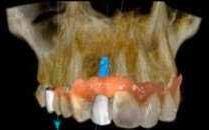

Az európai uniós rendeletekkel való harmonizáció keretében új szakvizsgák, feltételek, követelményrendszer alakult ki a hazai sztomatológiában. Megjelent az új orális implantológia szakvizsga, és egészen új szintre került a többi fogászati szakorvosi vizsga követelményrendszere is. Az új szakvizsgákhoz tartozó követelmények egyben a szakma új szabályainak is tekinthetőek, vagyis jelentős feladat elé állítják a rendelőket. A fejlődést a páciensek is nyomon követhetik az interneten keresztül, és ezzel új, és a réginél sokkal magasabb igényszintű fogászatot, implantológiát elvárásként fogalmazhatják meg. Ha ezt az új színvonalat, a fejlődést kevéssé követő fogorvosi rendelővel szemben várják el, akkor az ott végzett kezelések után kialakulhat a „konfliktus szituáció.” (1–3. képek)

Az implantológiában inkább a szájsebészeti jellegű témák voltak hangsúlyosak, a manuális eljárások dominanciája volt jellemző. Ma inkább a különleges csontpótlásokról, az előre megtervezett fogpótlásból (backwards planning = visszafelé tervezés) kiindult sebészeti tervezésről esik sok szó, ez vált követelménnyé. A digitális eljárások fölénybe kerültek a manuálisokkal szemben. A régi technológiák folyamatosan kikopnak a gyakorlatból. És itt is kérdés: Mi az, ami megfelel – még vagy már – a szakma szabályainak? Már csak emiatt is sok mindent újra kell gondolni (4–5. képek)